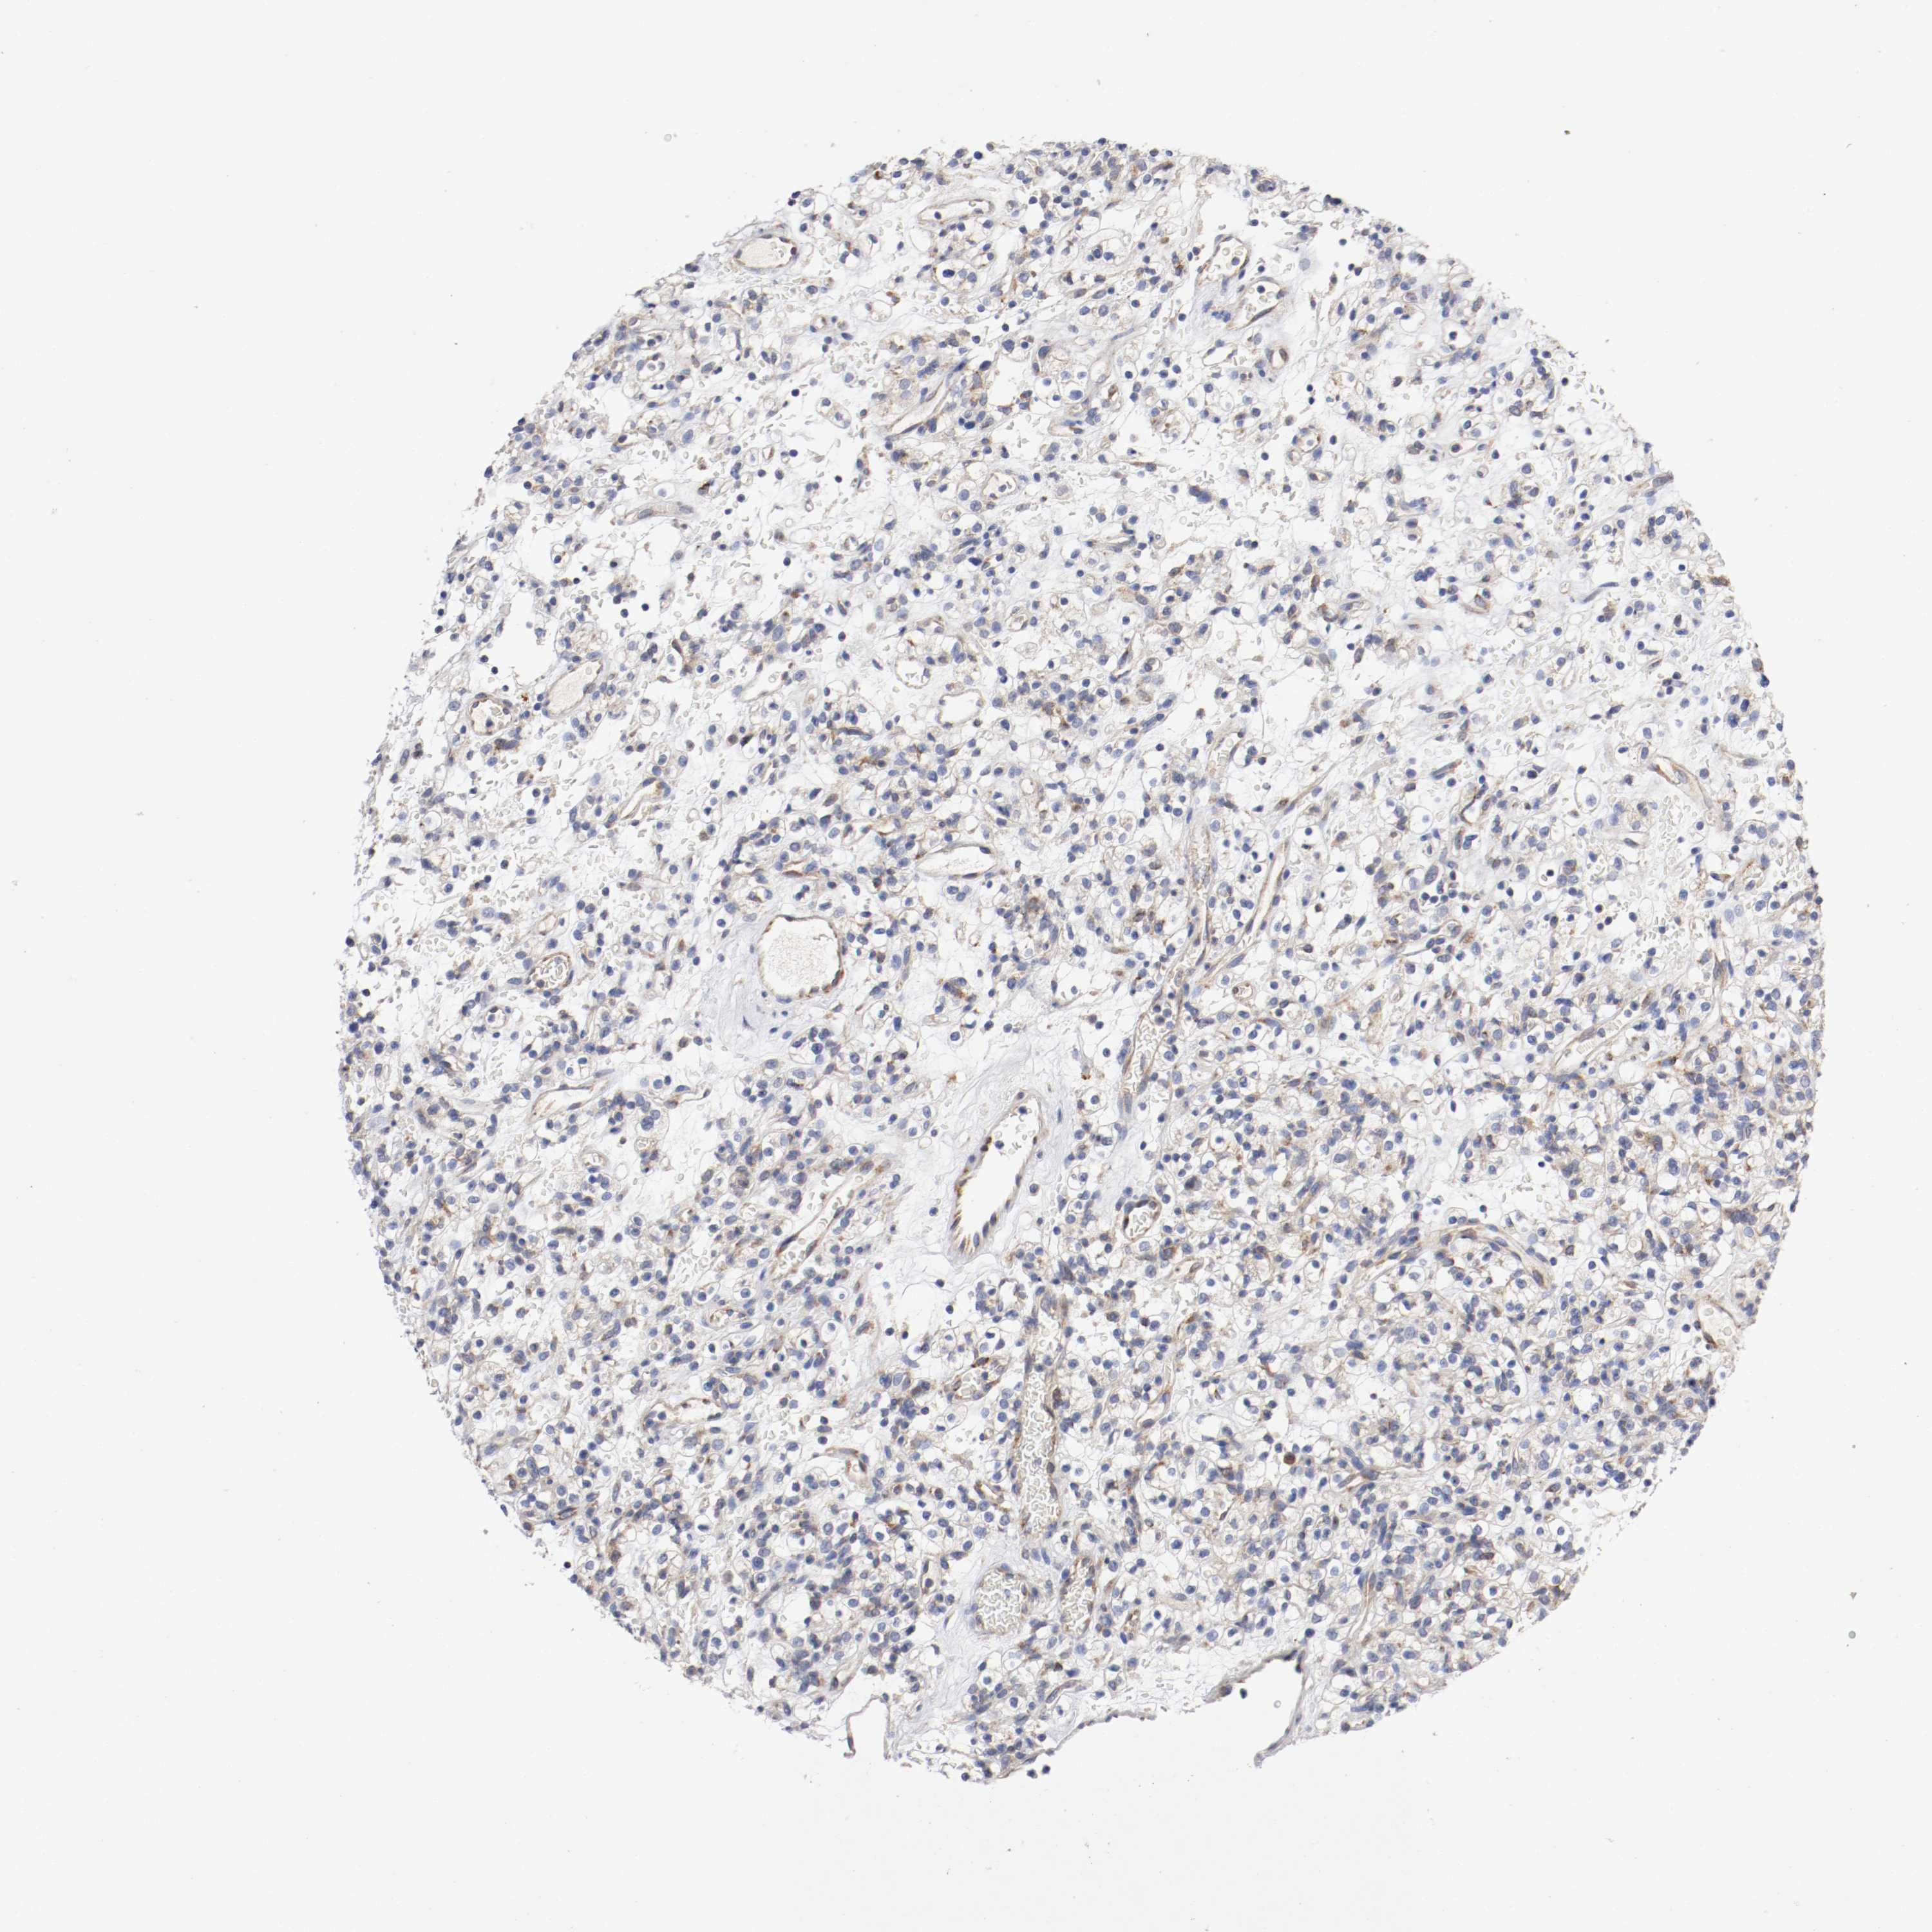

KIDNEY CHROMOPHOBE (TCGA) - Interactive survival scatter ploti

The Survival Scatter plot shows the clinical status (i.e. dead or alive) for all individuals in the patient cohort, based on the same data that underlies the corresponding Kaplan-Meier plots. Patients that are alive at last time for follow-up are shown in blue and patients who have died during the study are shown in red.

The x-axis shows the expression levels (FPKM) of the investigated gene in the tumor tissue at the time of diagnosis. The y-axis shows the follow-up time after diagnosis (years). Both axes are complimented with kernel density curves demonstrating the data density over the axes. The top density plot shows the expression levels (FPKM) distribution among dead (red) and alive patients (blue). The right density plot shows the data density of the survived years of dead patients with high and low expression levels respectively, stratified using the cutoff indicated by the vertical dashed line through the Survival Scatter plot. This cutoff is automatically defined based on the FPKM cutoff that minimizes the p-score. The cutoff can be changed by dragging the vertical line or by entering a cutoff value in the square labeled "Current cut-off".

Under the Survival Scatter plot the p-score landscape (black curve; left axis) is shown together with dead median separation (red curve; right axis). Dead median separation is the difference in median mRNA expression between patients who have died with high and low expression, respectively. It is calculated as follows: median FPKM expression of dead patients with high expression - median FPKM expression of dead patients with low expression. This is intended to aid the user in visually exploring custom cutoffs and the associated p-scores and dead median separation.

Individual patient data is displayed and can be filtered by clicking on one or more of the category buttons on the top of the page. Categories describing expression level and patient information include: high, low, alive, dead, female, male and tumor stages. The scale of the x-axis can be toggled between linear and log-scale by clicking on the "x log" button. Mouse-over function shows TCGA ID, patient information and mRNA expression (FPKM) for each patient.

& Survival analysisi

Kaplan-Meier plots summarize results from analysis of correlation between mRNA expression level and patient survival. Patients were divided based on level of expression into one of the two groups "low" (under cut off) or "high" (over cut off). X-axis shows time for survival (years) and y-axis shows the probability of survival, where 1.0 corresponds to 100 percent.

TRAF2 is not prognostic in Kidney Chromophobe (TCGA)

Best expression cut offi

Based on the FPKM value of each gene, patients were classified into two groups and association between prognosis (survival) and gene expression (FPKM) was examined. The best expression cut-off refers the FPKM value that yields maximal difference with regard to survival between the two groups at the lowest log-rank P-value. Best expression cut-off was selected based on survival analysis .

When clicking on this number, the vertical dashed line indicating cut-off, the interactive survival plot, and the Kaplan-Meier curve will be adjusted to show results based on the best expression cut-off.

: 17.68

Median expressioni

Median expression refers to the median FPKM value calculated based on the gene expression (FPKM) data from all patients in this dataset. When clicking on this number, the vertical dashed line indicating cut-off, the interactive survival plot, and the Kaplan-Meier curve will be adjusted to show results based on the median expression.

: N/A

Median follow up timei

Median follow up time refers to the median time (years) after diagnosis with this type of cancer, based on clinical data from all patients in this dataset.

P scorei

Log-rank P value for Kaplan-Meier plot showing results from analysis of correlation between mRNA expression level and patient survival.

N/A

5-year survival highi

5-year survival for patients with higher expression than the expression cutoff.

For melanoma and glioma, 3-year survival is shown.

5-year survival lowi

5-year survival for patients with lower expression than the expression cutoff.

TCGA RNA samplesi

RNA-seq data is reported as average FPKM (number Fragments Per Kilobase of exon per Million reads), generated by the The Cancer Genome Atlas (TCGA) .

Normal distribution across the dataset is visualized with box plots, shown as median and 25th and 75th percentiles. Points are displayed as outliers if they are above or below 1.5 times the interquartile range. FPKM values of the individual samples are presented next to the box plot.

Average pTPM 13.6

Number of samples 64